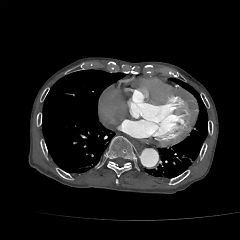

现病史:患者8小时前无明显诱因下出现头晕伴恶心呕吐,呕吐物为胃内容物,无视物旋转,无呕血黑便,无胸闷气促,无胸痛,遂至当地医院就诊查。CTA提示主动脉瘤,腹主动脉多发钙化,胸主动脉多发钙化斑块。

▶ 术前影像学资料

IV型胸腹主动脉瘤,瘤颈和双侧髂动脉严重扭曲,瘤体巨大,内脏分支血管开口角度倾斜

2. 左侧肱动脉入路,超选至降主动脉,更换8F-900mm长鞘,造影提示IV型胸腹主动脉瘤,累及双肾动脉。